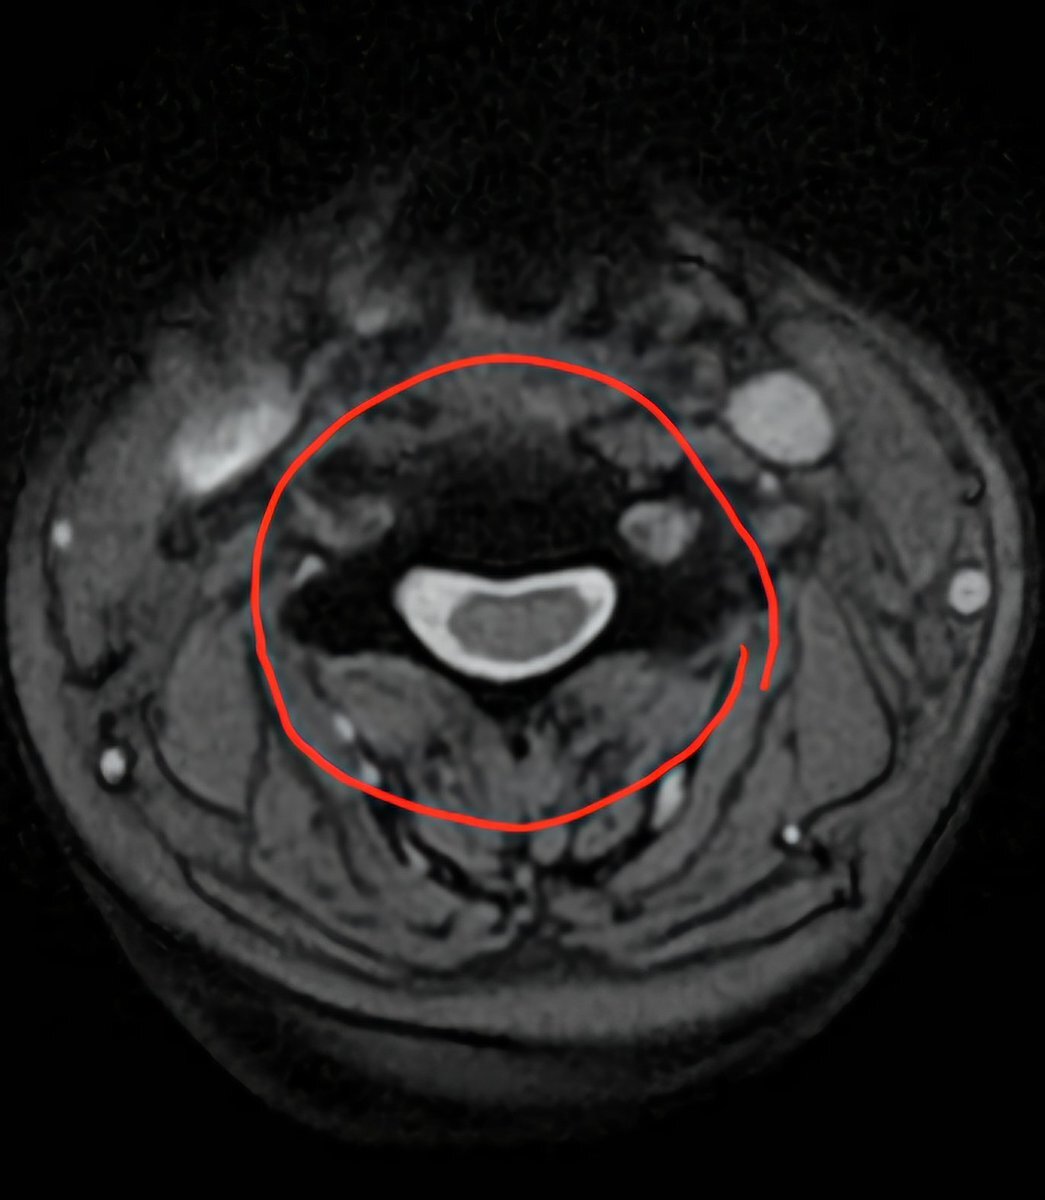

昨日診断された頸椎ヘルニアのMRI画像。縦に輪切りにされた5~6番目がずれてます。他2枚は横に輪切りにした画像。一枚は正常な頸椎で楕円になってますが、もう一枚はかなり潰された頸椎。ここが患部。なんか見てるだけで怖い。#頸椎ヘルニア #頚椎ヘルニア #椎間板ヘルニア pic.x.com/EpQGHwUqeI